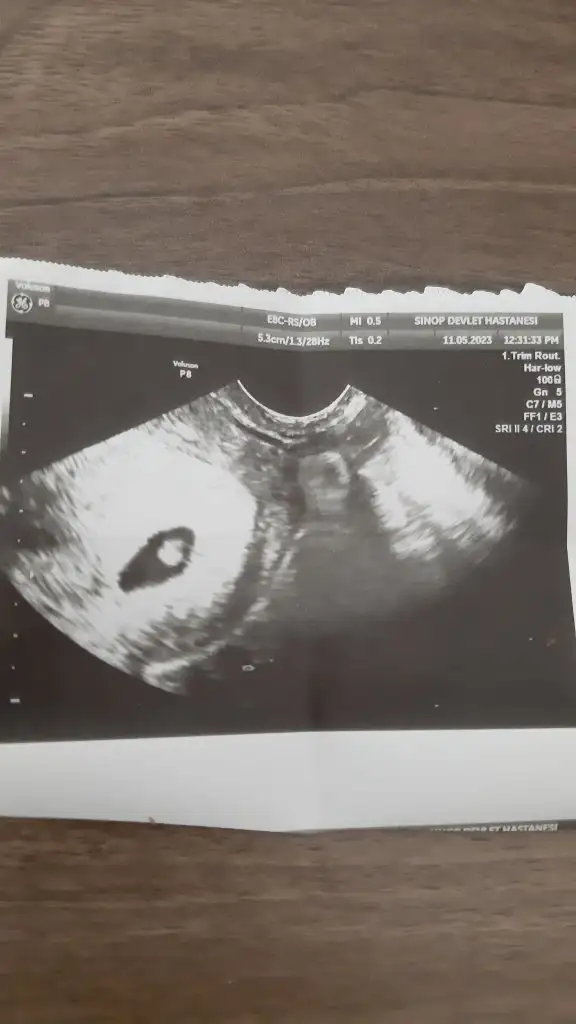

Karından usg lerde ayna etkisi yaratabiliyor. Sağı solda solu sağda gösterebiliyor. En doğrusu vajinal usgler. Vajinale göre solda bu bebiş kızmelegim can canımm bu bebiş vajınalde gecen haftaya gore diğer tarafta gozukuyo bu sefer kıza mı dondu acaba